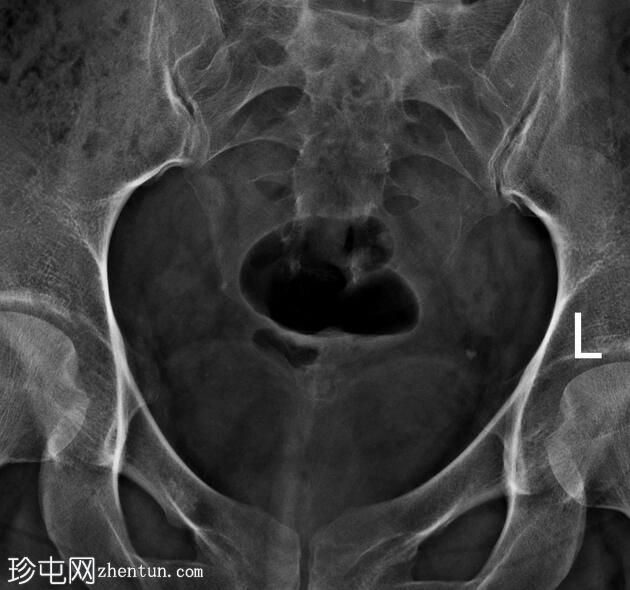

子宫位于盆腔正中线,形态及轮廓正常。

宫颈管长度及黏膜表面正常,扩张正常。

左侧输卵管充盈,管腔扩张,造影剂残留,无因输卵管积水导致的溢液。

右侧输卵管峡部造影剂显影中断,造影剂远端呈球状扩张。